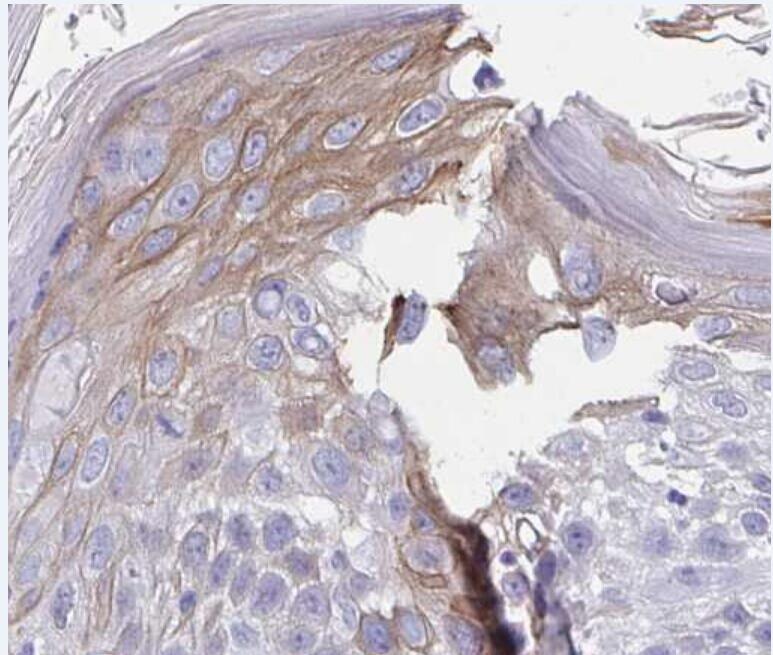

Immunohistochemical analysis of paraffin-embedded human breast cancer tissue, antibody was diluted at 1:200